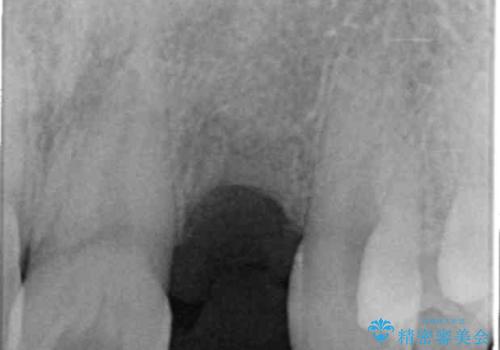

- 前歯の永久歯が元々なく、乳歯を失ったタイミングで前歯の審美性の回復を求めて来院されました。

前歯部にインプラントを埋入し、きれいに仕上げるためには骨の造成技術や歯肉の厚みを増すような処置を行い、インプラント周囲の環境を整備することが肝要です。